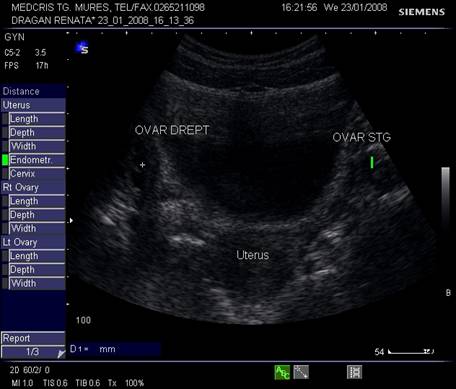

Fig. nr.347. Sectiune transversala ecografica transabdominala , cu uter si ovare premenarcha .

Fig. nr.349. Sectiune transversala prin pelvisul feminin , la ecografia abdominala postmenarcha, se remarca ovarele cu zone anecogene foliculare.

Vasele uterine apar in 1/3 externa a miometrului, cu contur neregulat, anecogene si usor de recunoscut la Doppler.

Ovarele. Sectiunea longitudinala directa, spre peretele lateral pelvin, la ecografia transvaginala, pune in evidenta ovarele cu forma elipsoidala. Acestea au structura ecografica relativ slab ecogena, in apropierea si sub vasele iliace.[5]

Marimea ovarelor: inainte de menopauza aproximativ 3,5 x 2,5 x 1,5 cm si aproximativ 2,0 x 1,5 x 1 cm dupa menopauza. Nu se poate aprecia volumul ovarian decat masurand cele trei diametre in planuri sagitale, oblice si coronale ale pelvisului.[1,2,9]